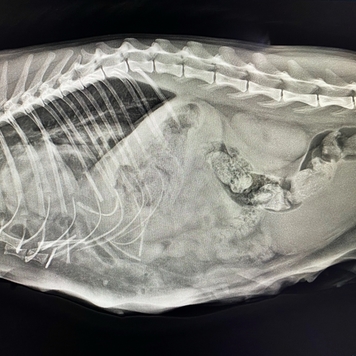

Несчастный случай, травмы и Василиса в Клинике БАРС на приеме неотложной помощи... Проведенная Rg-диагностика показала множественные переломы (один из них - открытый) и значительные внутренние повреждения со смещением органов брюшной полости в грудную клетку. Опытный ветеринарный врач, хирург [club223252442|Анна Сергеевна Кашина] знает, что в таких ситуациях медлить нельзя ни минуты, поэтому она взяла Василису на срочную операцию.

Период восстановления после травматической диафрагмальной грыжи варьируется по времени и зависит от тяжести повреждений внутренних органов, наличия кровотечения и еще ряда факторов. Травмы Василисы были очень серьезными, и, как оказалось в ходе операции, видимые переломы костей - это меньшее из зол. Прогноз был очень осторожным...